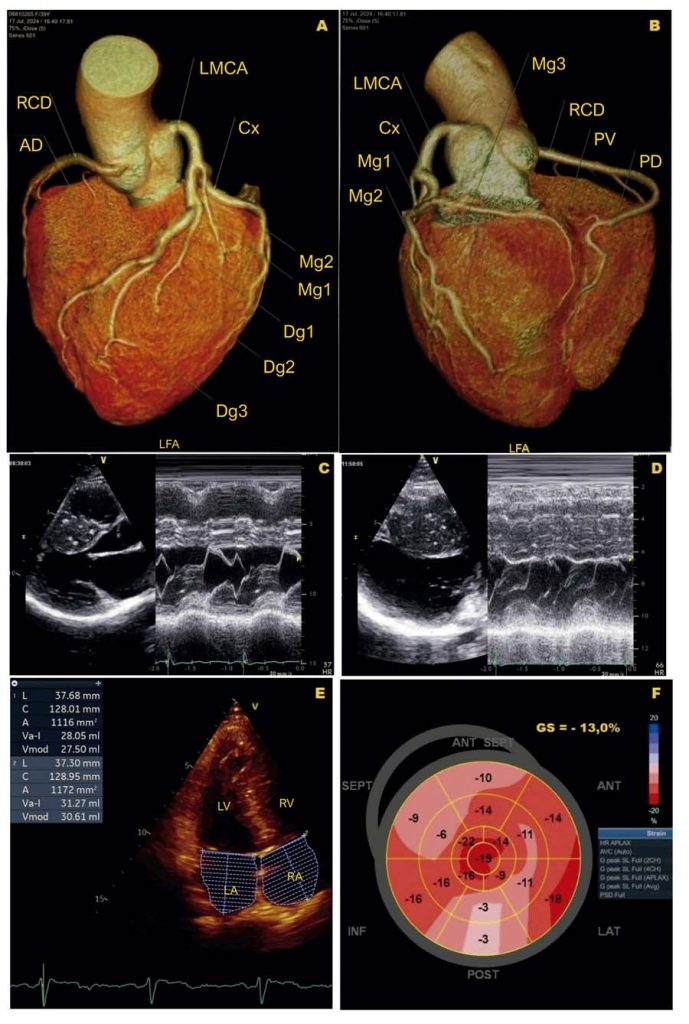

Hemodynamic Impact of Hypertrophic Cardiomyopathy at Rest and During Supine Bicycle Exercise: Additional Value of Postprandial Assessment

A patient with severe, symptomatic hypertrophic cardiomyopathy (HCM) without a significant left ventricular outflow tract (LVOT) gradient at rest requires further evaluation. During exercise echocardiography (EE) performed on a supine bicycle, a latent or underestimated dynamic obstruction may be identified in real time, with postprandial assessment being particularly relevant.